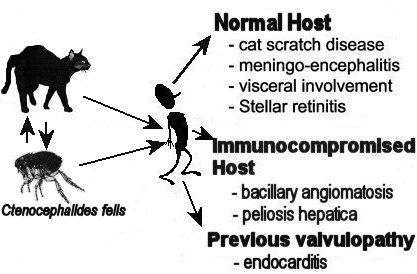

Cat Scratch Disease | Healthy Pets  From Cat Scratch Disease to Bartonellosis

From Cat Scratch Disease to Bartonellosis Cat scratch disease: MedlinePlus

Cat Scratch Fever: Causes, Symptoms  A Review on Cat Scratch Disease and it

A Review on Cat Scratch Disease and it  Cat Scratch Disease | Causes, Symptoms

A Review on Cat Scratch Disease and it  Cat Scratch Disease (Cat Scratch Fever

Cat Scratch Disease (Cat Scratch Fever  Cat-Scratch Disease

Cat-Scratch Disease  Bartonella infection - Symptoms